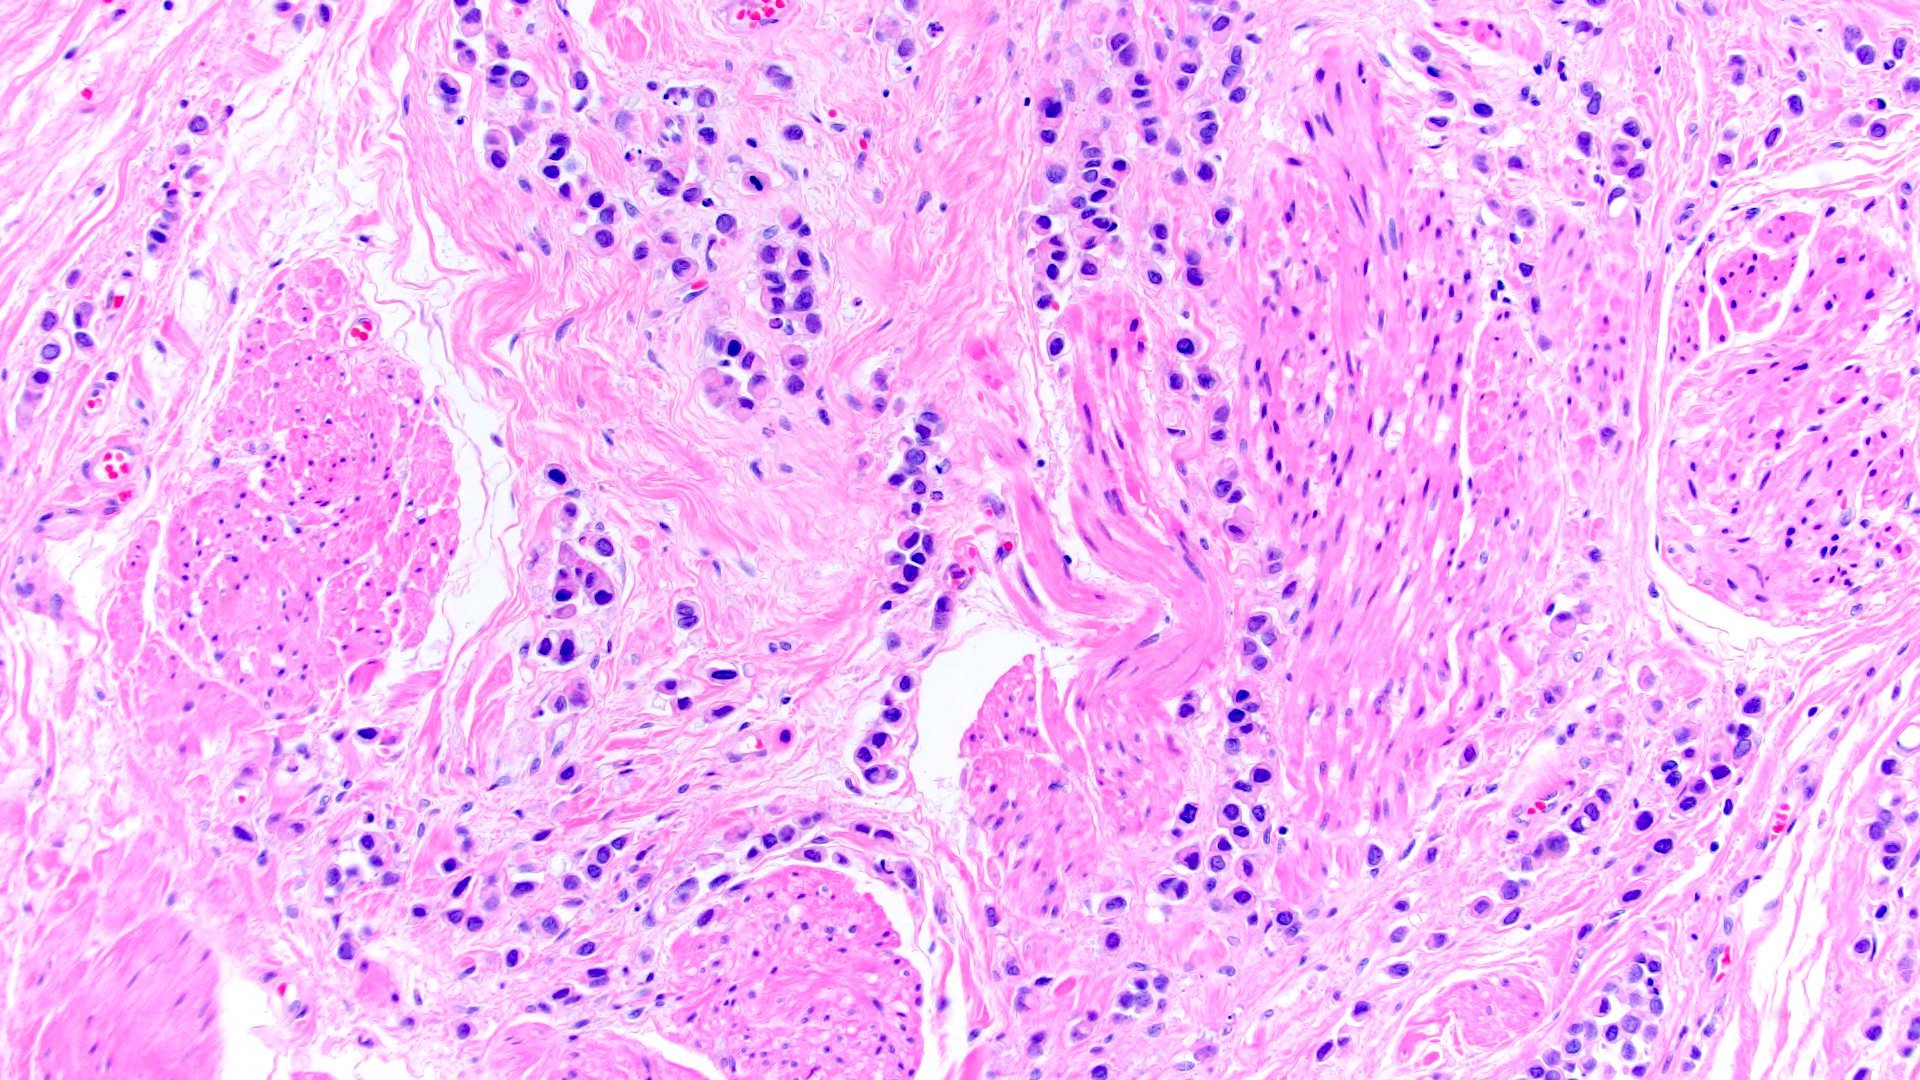

- Discohesive single cells with eccentrically placed nuclei and abundant eosinophilic cytoplasm

- Often deeply infiltrative but with minimal stromal reaction (Eur Urol Focus 2020;6:653)

- Further subclassified into classic, pleomorphic and desmoplastic subtypes:

- Pleomorphic: similar to classic but with pleomorphic nuclei and more atypia; can be rhabdoid and bizarre appearing (Hum Pathol 2019;90:27)

- Desmoplastic: plasmacytoid neoplastic cells with a surrounding desmoplastic stromal response (Hum Pathol 2019;90:27)

- Associated with sarcomatoid variant in 31% of cases (Hum Pathol 2019;90:27)

Microscopic (histologic) images

Contributed by Timothy Isaac Miller, M.D., M.A., Nicole K. Andeen, M.D. and Maria Tretiakova, M.D., Ph.D.

Contributed by Lisa Han, M.D. and Ricardo Lastra, M.D. (Case #510)